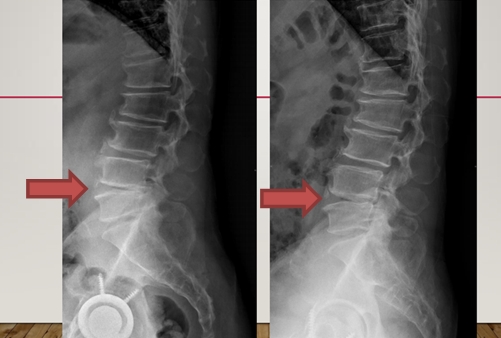

圖左側為腰椎治療前,右側為腰椎震波治療後,患者為腰椎椎間盤第四第五節突出導致椎間盤塌陷腰椎磨損,導致患者嚴重腰痛走路跛腳,經神經外科醫師判定需開刀,經三個月12次震波治療後,磨損復原,疼痛與跛腳復原。